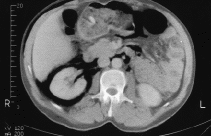

En la exploración física destacaban dolor a la palpación en FII y enfisema subcutáneo más pronunciado en hemiabdomen derecho. En la serie radiológica se incluyó: radiografía de abdomen (fig. 1) y de tórax (fig. 2) así como tomografía computarizada abdominal con ventana normal (fig. 3) y ventana modificada (fig. 4), evidenciándose retroneumoperitoneo bilateral con extensión a partes blandas (región del cuello).

Fig. 3.